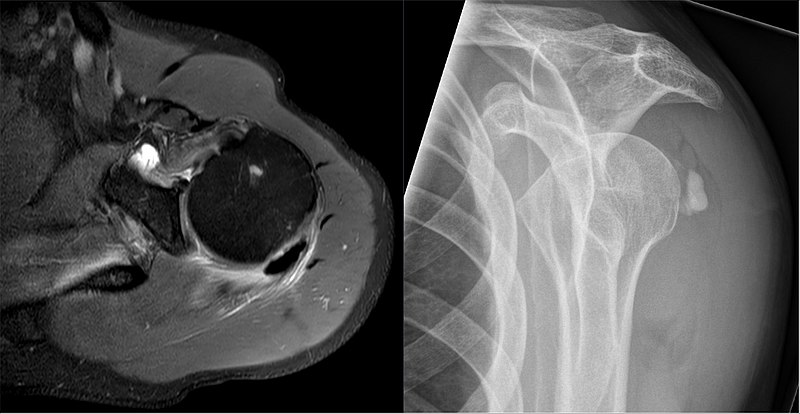

이 밖에 환자분들이 정밀검사를 원하셔서 요청하시는 CT나 MRI가 있을 수 있습니다만, CT 촬영은 석회 침착의 위치를 찾는데 3D적인 그림을 제공해준다는 점에서는 의미가 있지만, 치료 방침에 영향을 미칠 정도는 아니기에 일상적으로 추천되진 않습니다. MRI의 경우에는 앞서 언급한대로 석회 침착물이 용해되면서 발생하는 회전근개의 파열 정도를 파악하고, 수술적 처치가 필요할 정도로 손상된 부분이 있는지 확인하는 데에는 유용한 검사입니다.

석회성 건염은 어깨의 다른 질환들과 비슷한 증상을 보이는 경우가 많아 감별진단을 정확하게 해야 하는 경우가 많습니다. 이러한 감별진단을 위해서 앞서 언급한대로 초음파와 MRI가 큰 도움이 되기 때문에, 병원 방문시에 전문의 선생님께서 MRI 촬영을 권하신다면 이러한 이유 때문에 촬영해보자고 하시는 것이라 생각하시면 되겠습니다. 상대적으로 외국에 비해서 검사 비용이 저렴한 우리나라의 경우 이런 때 아주 큰 도움이 됩니다. (물론 환자분들 입장에선 큰 돈일 수 있지만.. 외국에 비해서 1/10밖에 안되는 금액으로 정밀 검사를 할 수 있다는 것은 정말 큰 축복입니다!)

외부의 균이 관절 내부로 침투해서 발생하는 화농성 관절염의 경우, 관절이 다 녹아버릴 수 있는 위험한 질환이기에 조기 감별이 매우 중요합니다. 이를 감별하기 위해서는, 극심한 통증이 발생한 환자에서 어깨 주변의 열감이 있거나, 어깨 통증으로 인해 침이나 주사치료 등 침습적인 치료를 받은 적이 있는 환자의 경우 지체없이 혈액검사를 통해 염증 수치가 상승했는지 파악해야합니다. 또한 MRI검사를 통해 어깨 관절 내의 농양이 있지는 않은지 확인해 볼 수 있으며, 관절액을 직접 빼내는 관절액 천자 검사를 통해 농이 생겼는지 직접 확인하는 방법도 있습니다. 화농성 관절염은 발견되는 즉시 응급수술해야하는 질환이므로 이러한 검사를 하는데 있어서 고민해서는 안됩니다!